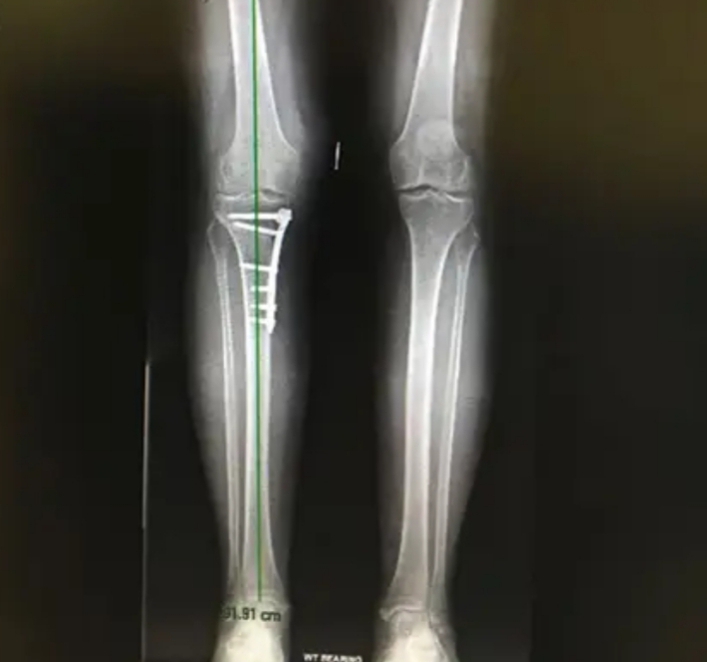

During surgery, the bone is either opened to create a gap or reshaped by removing a wedge. The new position is stabilized using metal plates and screws. Recovery includes a period of reduced weight-bearing, followed by physiotherapy to restore strength and mobility. Most patients gradually return to normal activities over time.